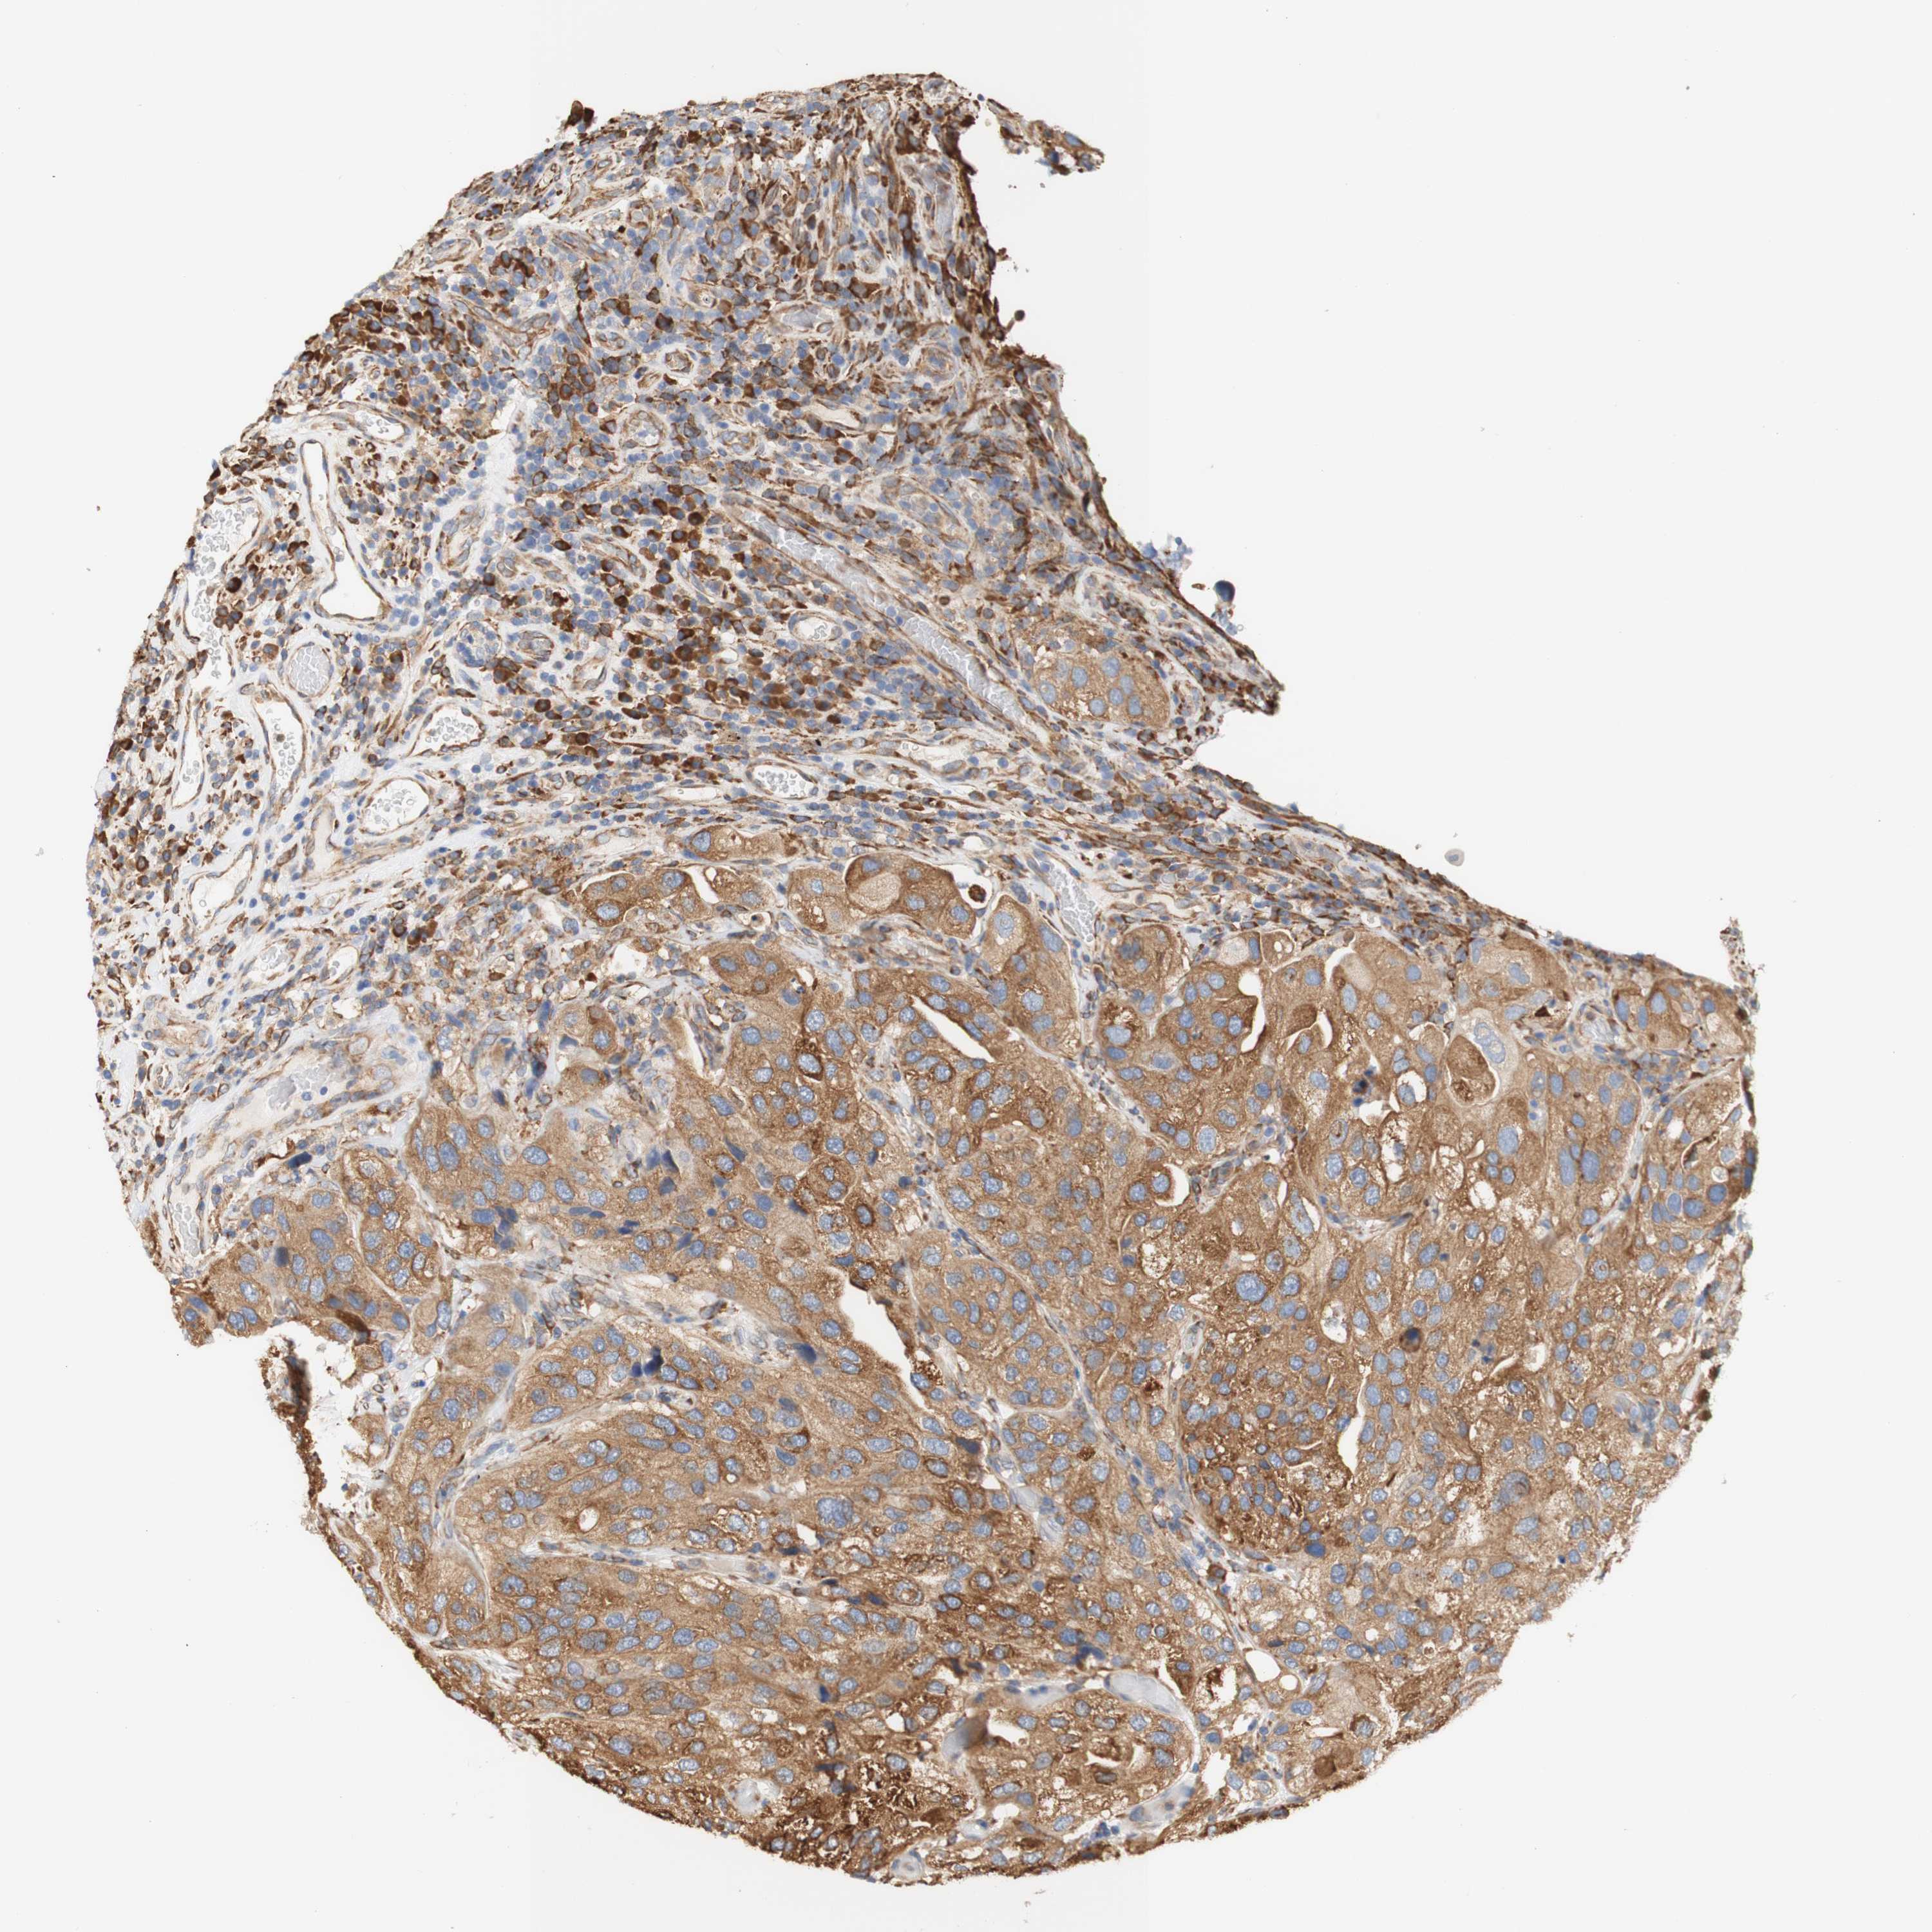

UROTHELIAL CANCER - Protein expressioni

A mouse-over function shows sample information and annotation data. Click on an image to view it in a full screen mode. Samples can be filtered based on level of antibody staining by selecting one or several of the following categories: high, medium, low and not detected. The assay and annotation is described here.

Note that samples used for immunohistochemistry by the Human Protein Atlas do not correspond to samples in the TCGA dataset.

Antibody stainingi

Antibody staining in the annotated cell types in the current human tissue is reported as not detected, low, medium, or high, based on conventional immunohistochemistry profiling in selected tissues. This score is based on the combination of the staining intensity and fraction of stained cells.

Each image is clickable and will lead to virtual microscopy that enables deeper exploration of all samples and also displays staining intensity scores, fraction scores and subcellular localization as well as patient and tissue information for each sample.

Antibody HPA011811

Staining

High

Medium

Low

Not detected

Intensity

Strong

Moderate

Weak

Negative

Quantity

>75%

75%-25%

<25%

None

Location

Nuclear

Cytoplasmic/membranous

Cytoplasmic/membranous,nuclear

Urothelial carcinoma, Low grade

Urothelial carcinoma, High grade